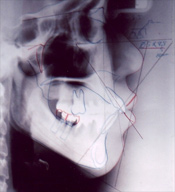

術前のレントゲン写真

埋入後のレントゲン写真

(Φ5×11.5〜10oのインプラント2本使用)